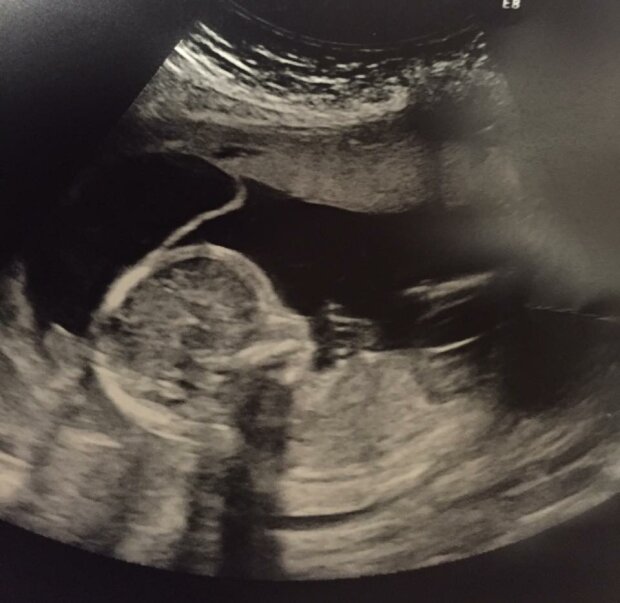

Byla připravena na to nejhorší. Pak ale uslyšela zprávy, které jí zase obrátily život vzhůru nohama. Během ultrazvuku si doktor všiml dvou chlapců a jedné dívky. Courtney se chystala porodit trojčata!

Bohužel, Courtney cestovala mezi nadějí a zoufalstvím. Ve 25. týdnu těhotenství žena slyšela další tragické zprávy. Doktor jí řekl, že nemůže cítit tep jednoho dítěte.

Obrázek z google.com